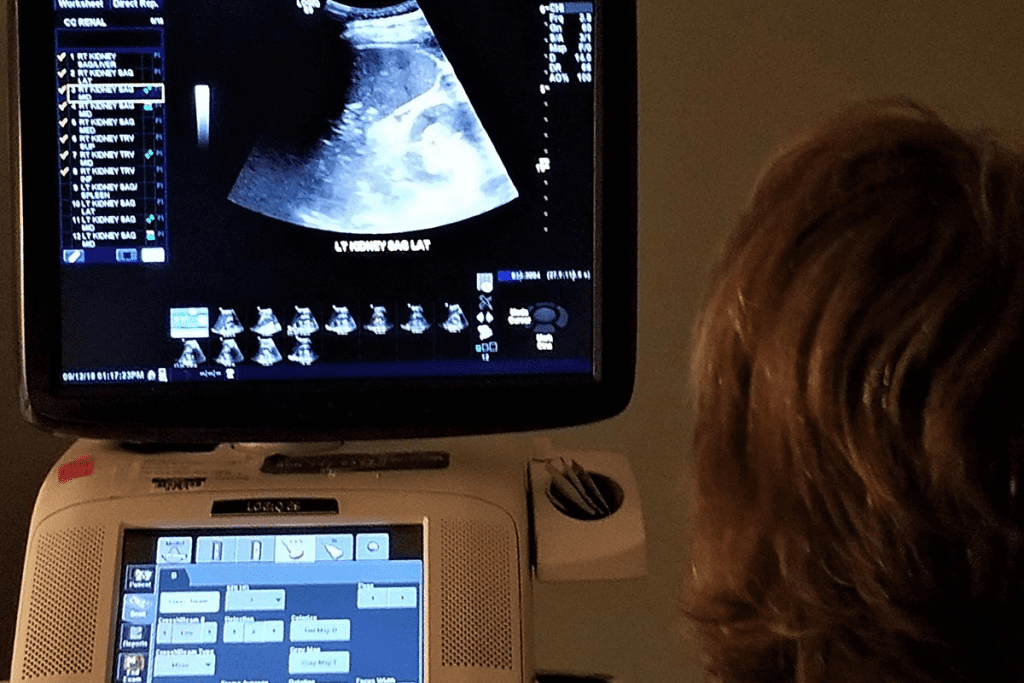

Renal Ultrasonography

Renal ultrasonography is a vital tool for checking the kidneys and nearby areas. It spots problems like cysts, tumors, and infections. Renal ultrasonography also looks at the size and shape of the kidneys, helping us plan treatment.